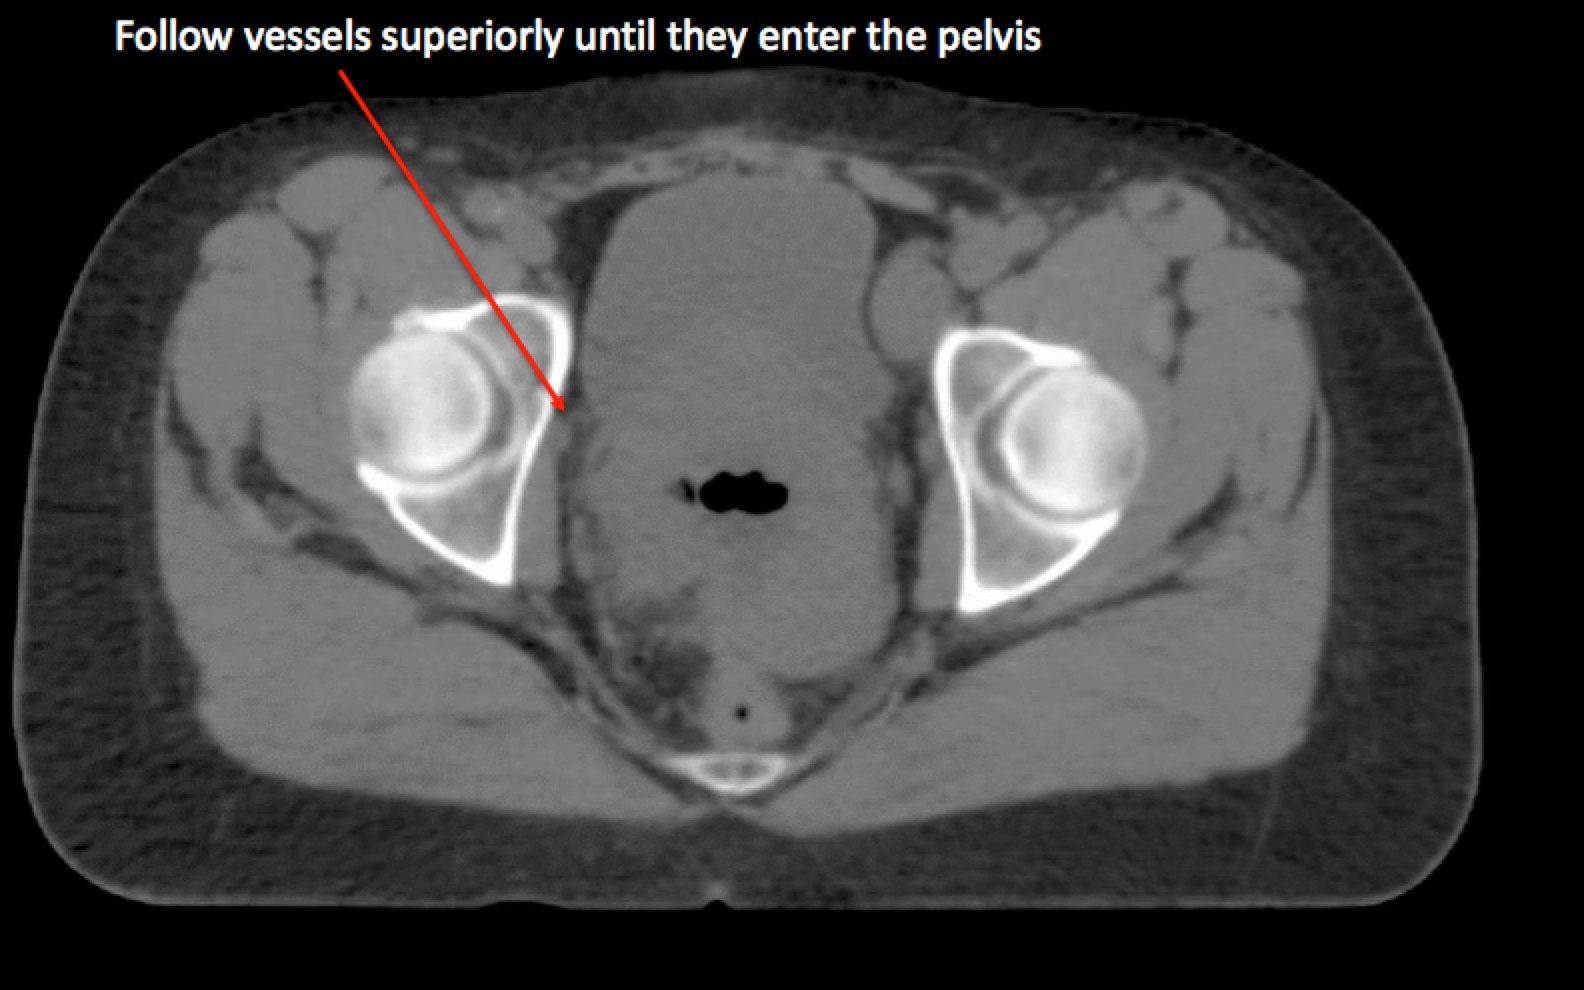

To identify the obturator nodes the following landmarks may be used. (Note: this works for any pelvis where one wishes to find the obturator nodes):